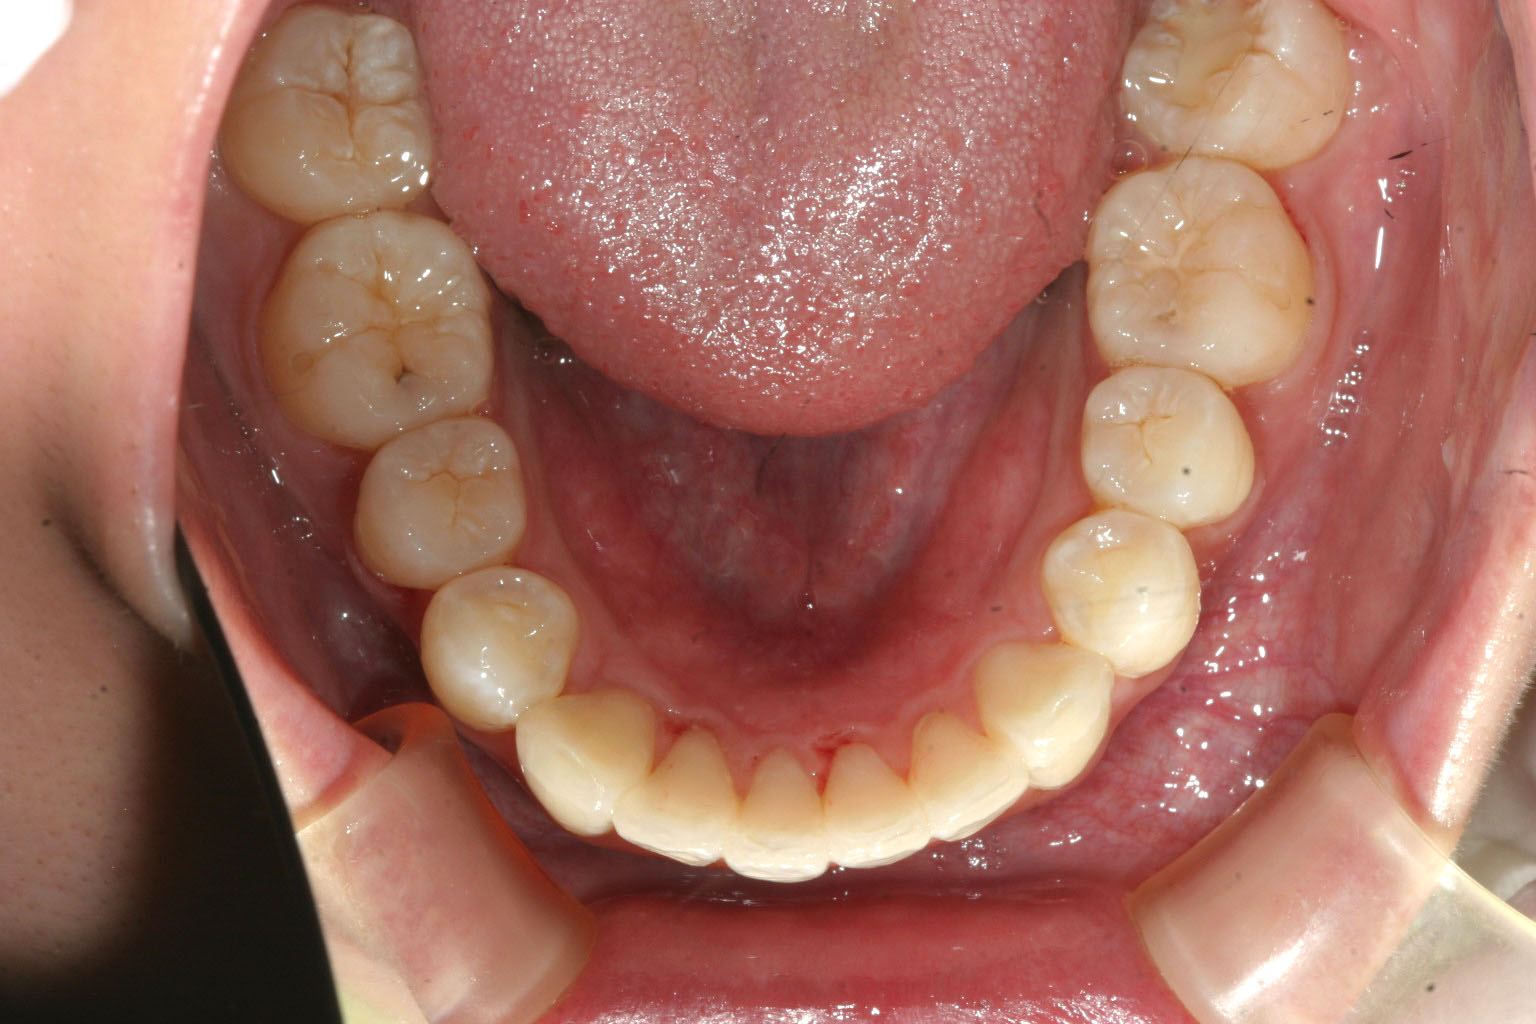

下顎もこうして歯列だけ見るとほぼ綺麗な状態です。

下顎はそのまま歯列を整えました。